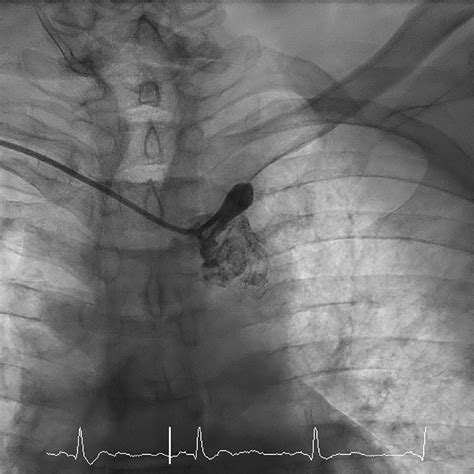

1. Thrombolytic Therapy: Using "clot-busting" drugs, such as tPA, to dissolve an existing blockage if administered within the critical window after symptom onset.

3. Endovascular Stenting: A minimally invasive procedure where a small mesh tube is placed inside the artery to hold it open and restore blood flow.